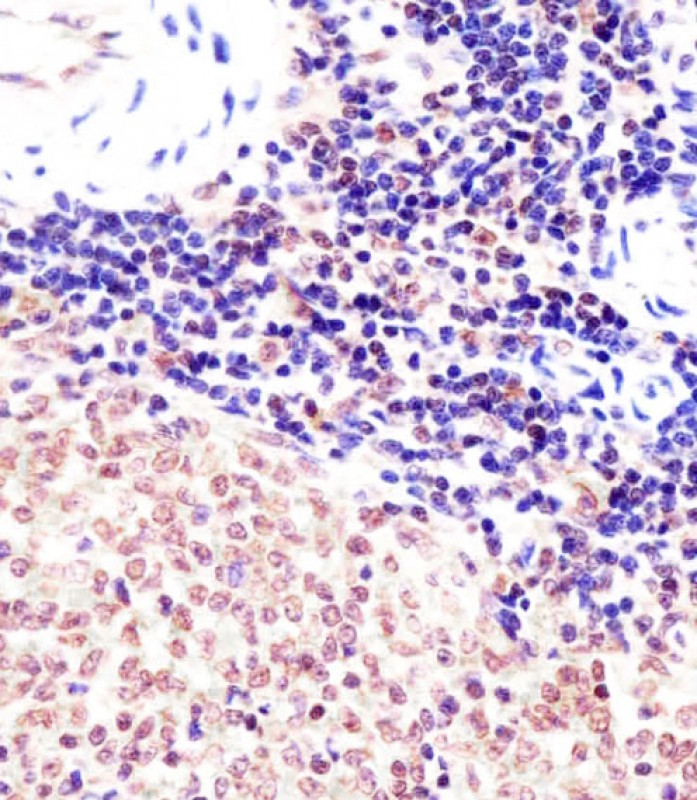

| IHC | 1/100-1/500 | Human,Mouse,Rat |

| Immunogen | This mouse Suz12 antibody is generated from a rabbit immunized with a KLH conjugated synthetic peptide between 381-395 amino acids from the Central region of mouse Suz12. |